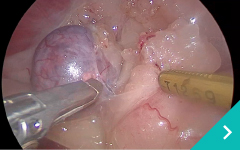

ミニマム創内視鏡下手術は腹腔鏡だけでは対処ができないような手術の際に、お腹にラッププロテクターという器具を設置して行う腹腔鏡と開腹手術を組み合わせた手術です。